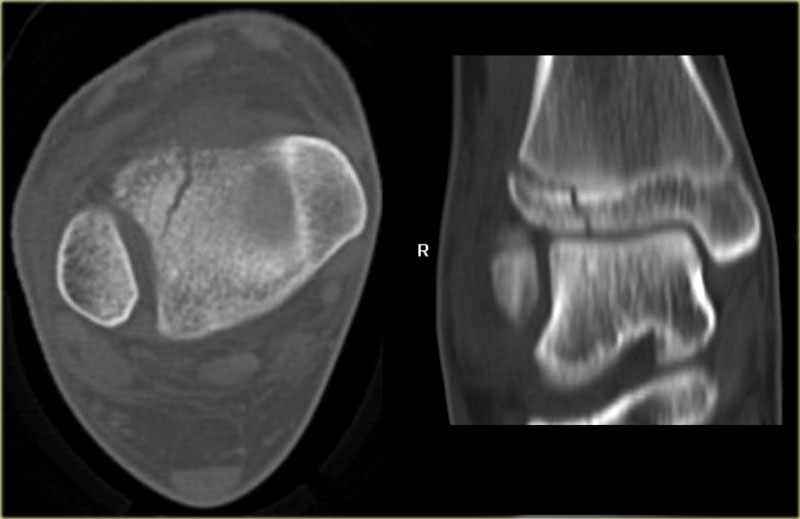

The x-ray shows a subtle Tillaux fracture, which is better appreciated on the CT-images.

Study these images carefully and remember the stages of an exorotation injury.

What is going on here?

There is a Tillaux fracture due to avulsion of the anterolateral part of the distal tibia by the anterior syndesmosis.

This can be a stage 2 of a Weber C fracture.

Stage 1 is rupture of the medial collateral ligaments and stage 3 is a fibula fracture above the level of the syndesmosis.

So now we start looking for stage 4, which is rupture or avulsion of the posterior syndesmosis.

Do you now see the tertius fracture on the axial CT-image?

This patient has an unstable ankle injury and a syndesmotic screw needs to be inserted.

There is a subtle widening of the lateral part of the growth plate of the right ankle.

There is also a very subtle fracture through the epiphysis.

Continue with the CT.

The CT-images show a epiphysiolysis fracture Salter Harris type 3.

This juvenile Tillaux is especially seen in young athletes.

Always look for higher stages of an exorotation injury.